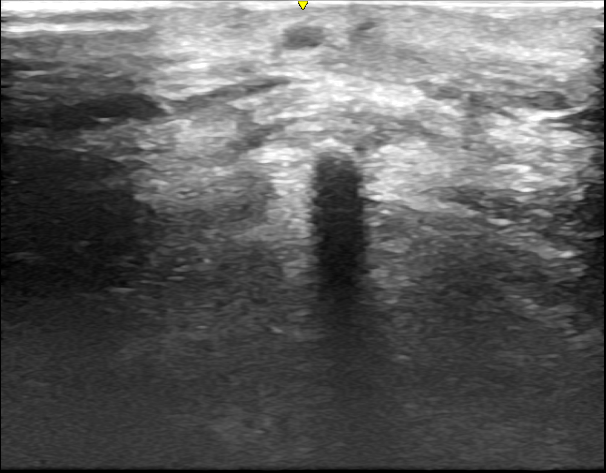

初回の再発

初回の再発を肉眼的には完全摘出